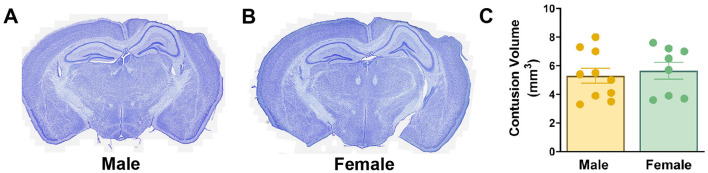

Methods: In-vivo labeling of NPCs and tracking of their morphological development into a granule cell was achieved using an inducible Cre recombinase driven by the Ascl1 promoter in a CAG-floxStopTom reporter mouse. Ascl1 is a basic helix-loop-helix transcription factor transiently expressed in NPCs and activated NSCs in the dentate gyrus of the adult mammalian brain. To specifically label NPCs born acutely after TBI, tamoxifen was delivered to mice on days 2 and 3 postinjury. Mice survived to 6 weeks after TBI to allow for full neuronal maturation of tdTomato-labeled NPCs.

Results: At 6 weeks postinjury, numbers of tdTomato-positive granule cells were significantly reduced in the ipsilateral hippocampus of brain-injured mice compared to controls, with a more pronounced decrease in males. Further, posttrauma-born neurons in males, but not females, exhibited impaired dendritic development. Neurons born after injury extended axons which formed synaptic terminals within the CA3 region. Numbers of mossy fiber boutons were significantly decreased in injured males compared to naïve males or to injured females. Potential forms of plasticity were observed in brain-injured females, including increased neurogenesis in the contralateral hippocampus and increased mossy fiber bouton volume. Together these data suggest a neurogenic advantage in females after injury.